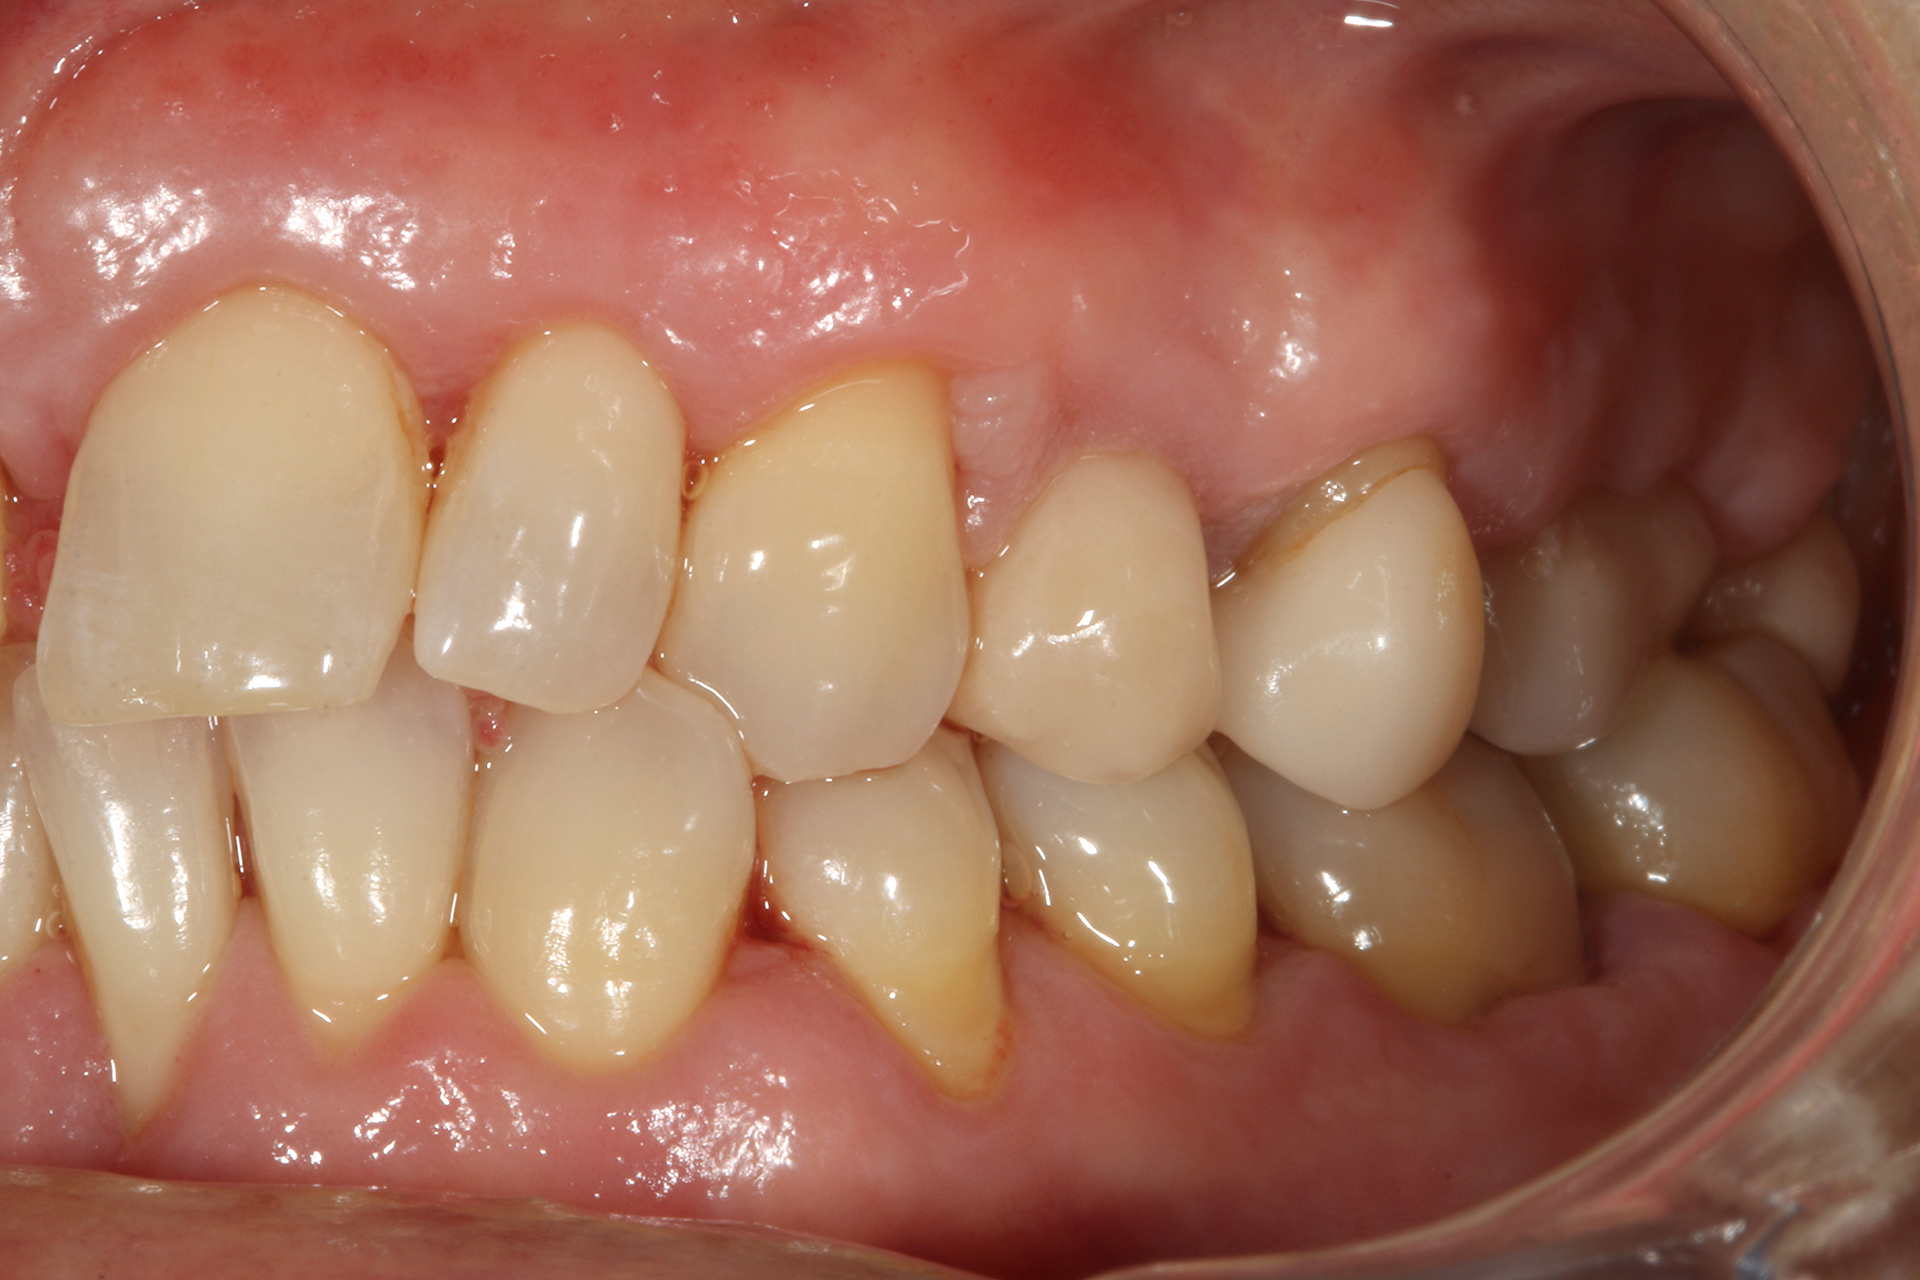

Il 20% degli impianti è stato posizionato nella mandibola (per lo più in posizione 47) e il restante 80% nel mascellare superiore (il 20% in posizione 16 e il 20% in posizione 25). Gli impianti posizionati nel mascellare superiore hanno trovato un osso tipo IV, mentre gli impianti posizionati nella mandibola hanno trovato un osso tipo III. Gli impianti utilizzati hanno un diametro compreso tra 4.0 e 4,5 mm (il 66.7% sono da 4.0 mm) e una lunghezza compresa tra 4.5 mm e 7.5 mm (il 53.3% sono lunghi 7.5 mm). Nell’86.7% dei casi non è stato eseguito alcun procedimento chirurgico aggiuntivo; in un caso, due impianti hanno previsto in rialzo di seno transcrestale con PRGF-Endoret e osso autologo. Nel 93.3% dei casi la protesizzazione ha previsto ponti avvitati a più elementi; un impianto è stato protesizzato mediante elemento singolo avvitato con componente transepiteliale. Il follow-up medio è stato di 12.4 ± 1.05 mesi dal carico. Il 100% degli impianti è sopravvissuto, senza complicanze né chirurgiche né protesiche. La perdita di osso media a 12 mesi è stata mesialmente di 0.15 ± 0.74 mm e distalmente di 0.13 ± 0.85 mm. La Figura 4 mostra l’osso perso su un singolo impianto e le Figure 5-14 illustrano un caso clinico rappresentativo.

Nella serie di casi clinici che abbiamo presentato, la combinazione di impianti Core-X® con il protocollo di chirurgia guidata Stop & Guide® è clinicamente efficace nel trattamento di casi caratterizzati da osso a bassa densità, anatomia compromessa o spazio interprossimale limitato.

La macro geometria implantare consente una densificazione ossea controllata e un’alta stabilità primaria senza manovre chirurgiche invasive.

Il sistema driver guidato consente un posizionamento implantare protesicamente guidato e preciso, minimizzando l’errore umano e preservando l’osso marginale.